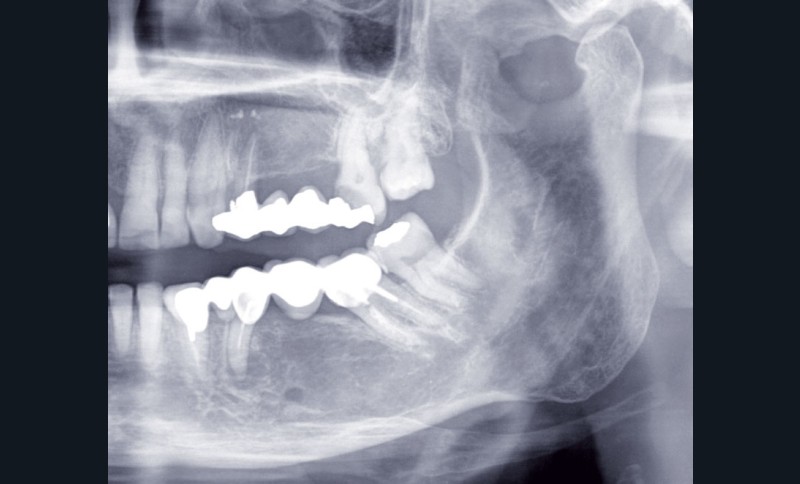

Au maxillaire, 3 implants Astra Tech Implant EV (Dentsply) sont posés en un temps chirurgical. Une empreinte pick-up sera réalisée après 4 mois de cicatrisation.